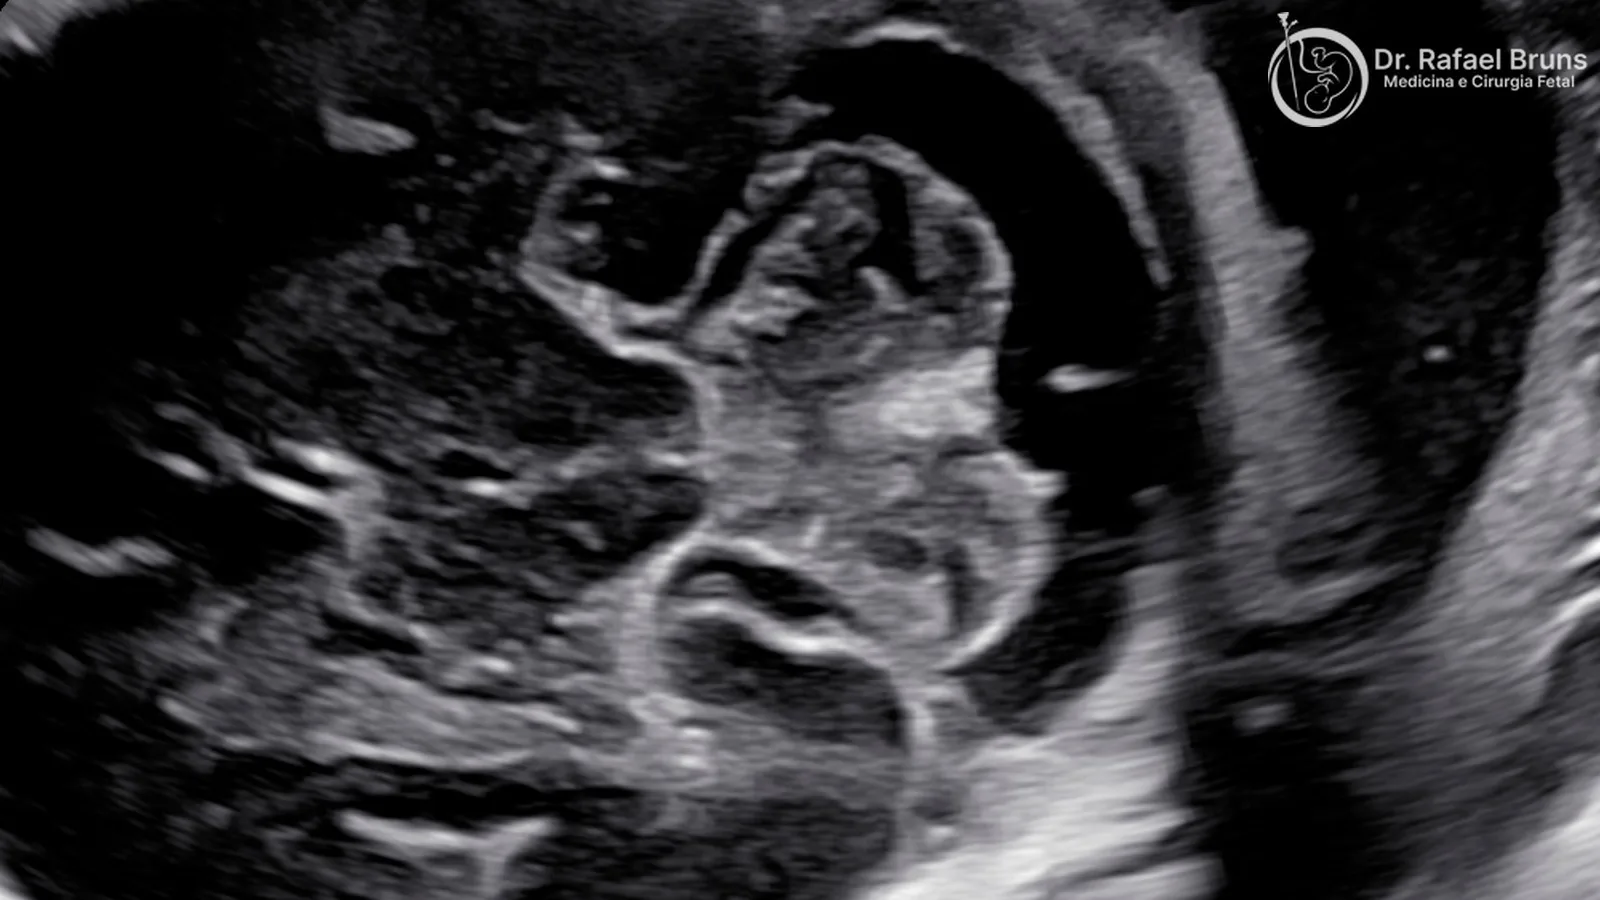

A neurossonografia fetal é um exame de ultrassom especializado voltado exclusivamente para o sistema nervoso central do feto — o cérebro, o cerebelo e a coluna vertebral. Diferente do ultrassom morfológico de segundo trimestre, que avalia todos os órgãos do bebê em uma varredura sequencial, a neurossonografia dedica todo o exame ao neuroeixo, com técnica e tempo específicos para isso.

A diferença técnica mais importante está nos planos utilizados. O morfológico avalia o crânio fetal principalmente em planos axiais (cortes horizontais). A neurossonografia incorpora planos sagitais, parassagitais e coronais — cortes que permitem visualizar estruturas que, em ângulos convencionais, ficam parcialmente ocultas ou mal definidas. O exame também pode usar recursos 3D e 4D para complementar a avaliação quando necessário.

A neurossonografia parte de onde o morfológico termina. Dedica todo o exame ao SNC, usa planos adicionais (sagital, parassagital e coronal, além dos axiais do morfológico) e avalia estruturas que não fazem parte do protocolo do morfológico convencional. A comparação técnica documentada em estudos mostra que a neurossonografia tem potencial diagnóstico significativamente superior ao morfológico para malformações complexas do SNC.